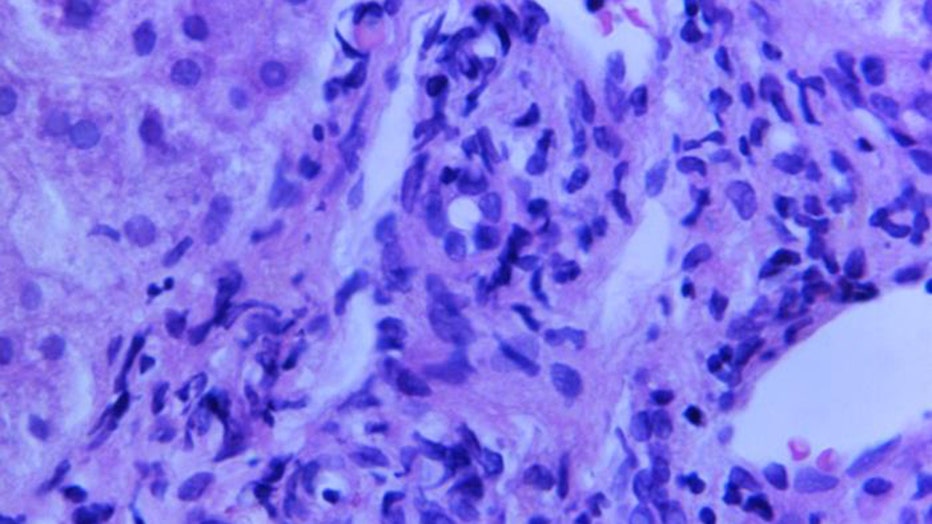

CDC_liver_biopsy_viral_hepatitis_file.jpg

A magnified photomicrograph of liver tissue infected by viral hepatitis. (CDC File Image)